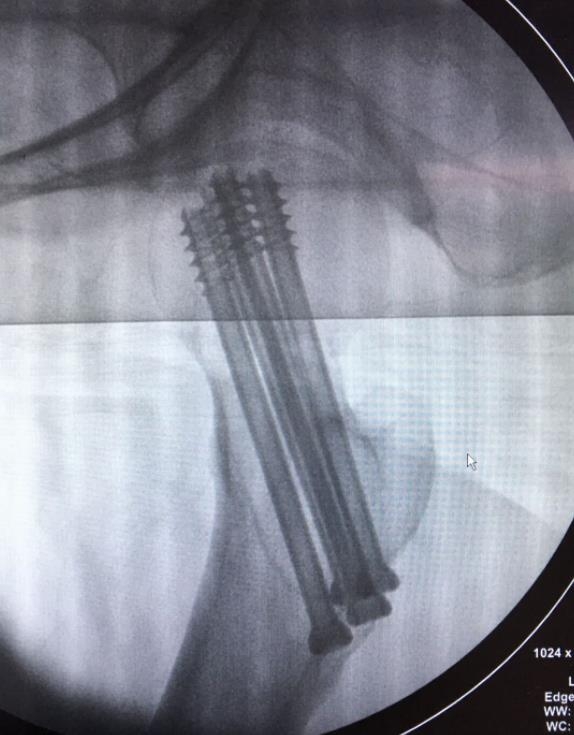

闭合复位经皮固定手术步骤

1、经皮沿股骨颈轴线置入空心钉导针,确保导针平行;

2、标准放置螺钉为倒三角形,其中下方螺钉在股骨矩,后方螺钉在后方骨皮质、研究发现倒三角形平行三枚螺钉能提供最佳的固定强度;

3、螺钉位于股骨颈四周,特别是后侧及下方,避免低于小转子方向进针,可能导致术后转子下骨折;

4、两个平面透视导针位置良好后切开皮肤,空心钻铭孔,导针引导下拧入空心钉,空心钉确保所有螺纹位于骨折线近端,螺钉头应距离软骨下骨5mm。

空心钉固定的三原则:“贴边、平行、倒品”

1、贴边是指3枚螺钉在股骨颈内,尽量靠近外围皮质。这样3枚螺钉作为一个整体,对整个骨折面可形成面状加压,如果3枚螺钉不够离散,更趋于点状加压,稳定性较差,不能较好地对抗扭转和剪切。

有研究显示,在侧位片上,螺钉的前后分布越分散,骨折不愈合发生率越低。J Bone Joint Surg Br. 2005 May: 87(5): 632-4.

图1 3枚螺钉在股骨颈内的理想位置

2、倒品有更明显的生物力学优势,CORR曾发表美国学者的一项生物力学研究,对比两种固定方式出现再骨折的负荷大小,发现倒三角再骨折的平均负荷11330N,而正三角仅7795N,差异明显,也就是说倒三角形固定可使再骨折的负荷提升45%。

图2 倒品字固定

3、平行生物力学更稳定。